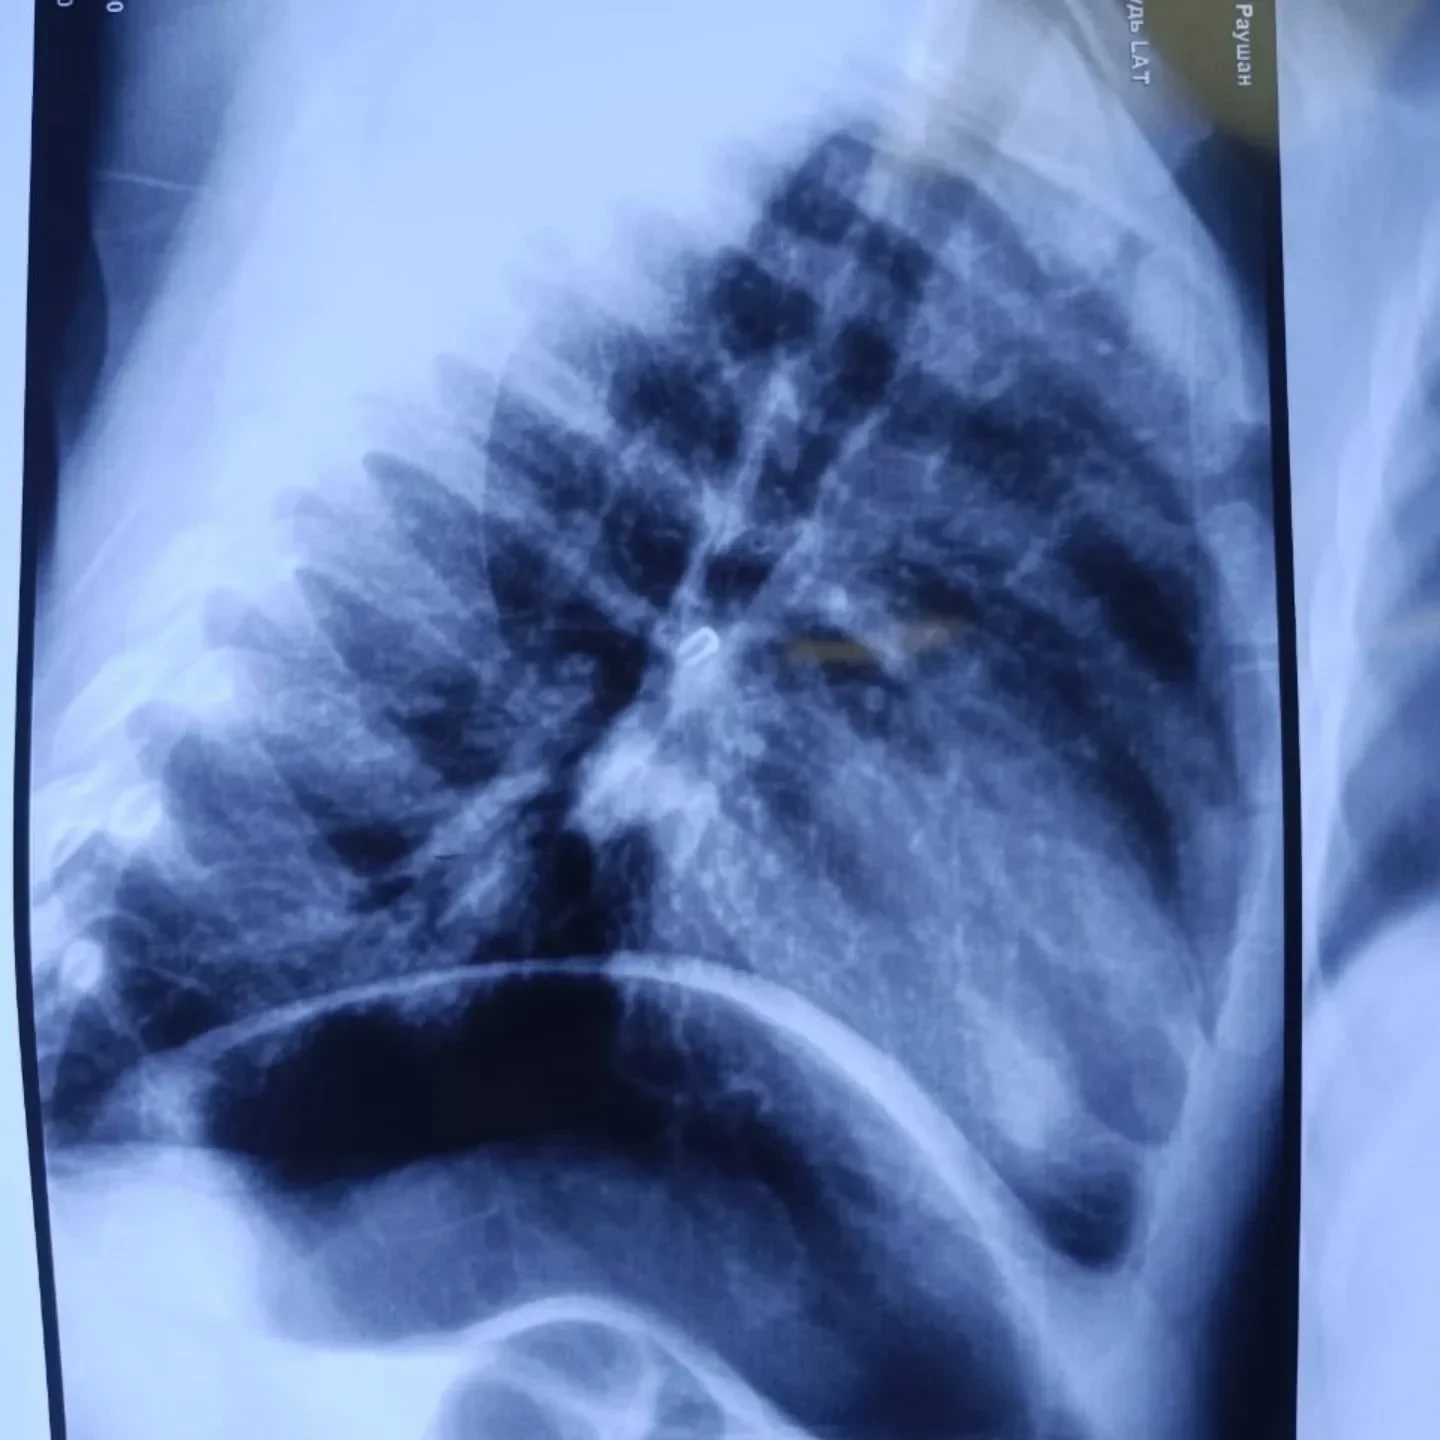

При поступлении в больницу состояние малыша оценивали как тяжелое, так как у него наблюдалась дыхательная недостаточность. Рентгеновское исследование выявило инородное тело в области правого главного бронха.

Команда врачей провела ригидную бронхоскопию под общим наркозом и успешно извлекла застрявший предмет, оказавшийся маленькой бусинкой.